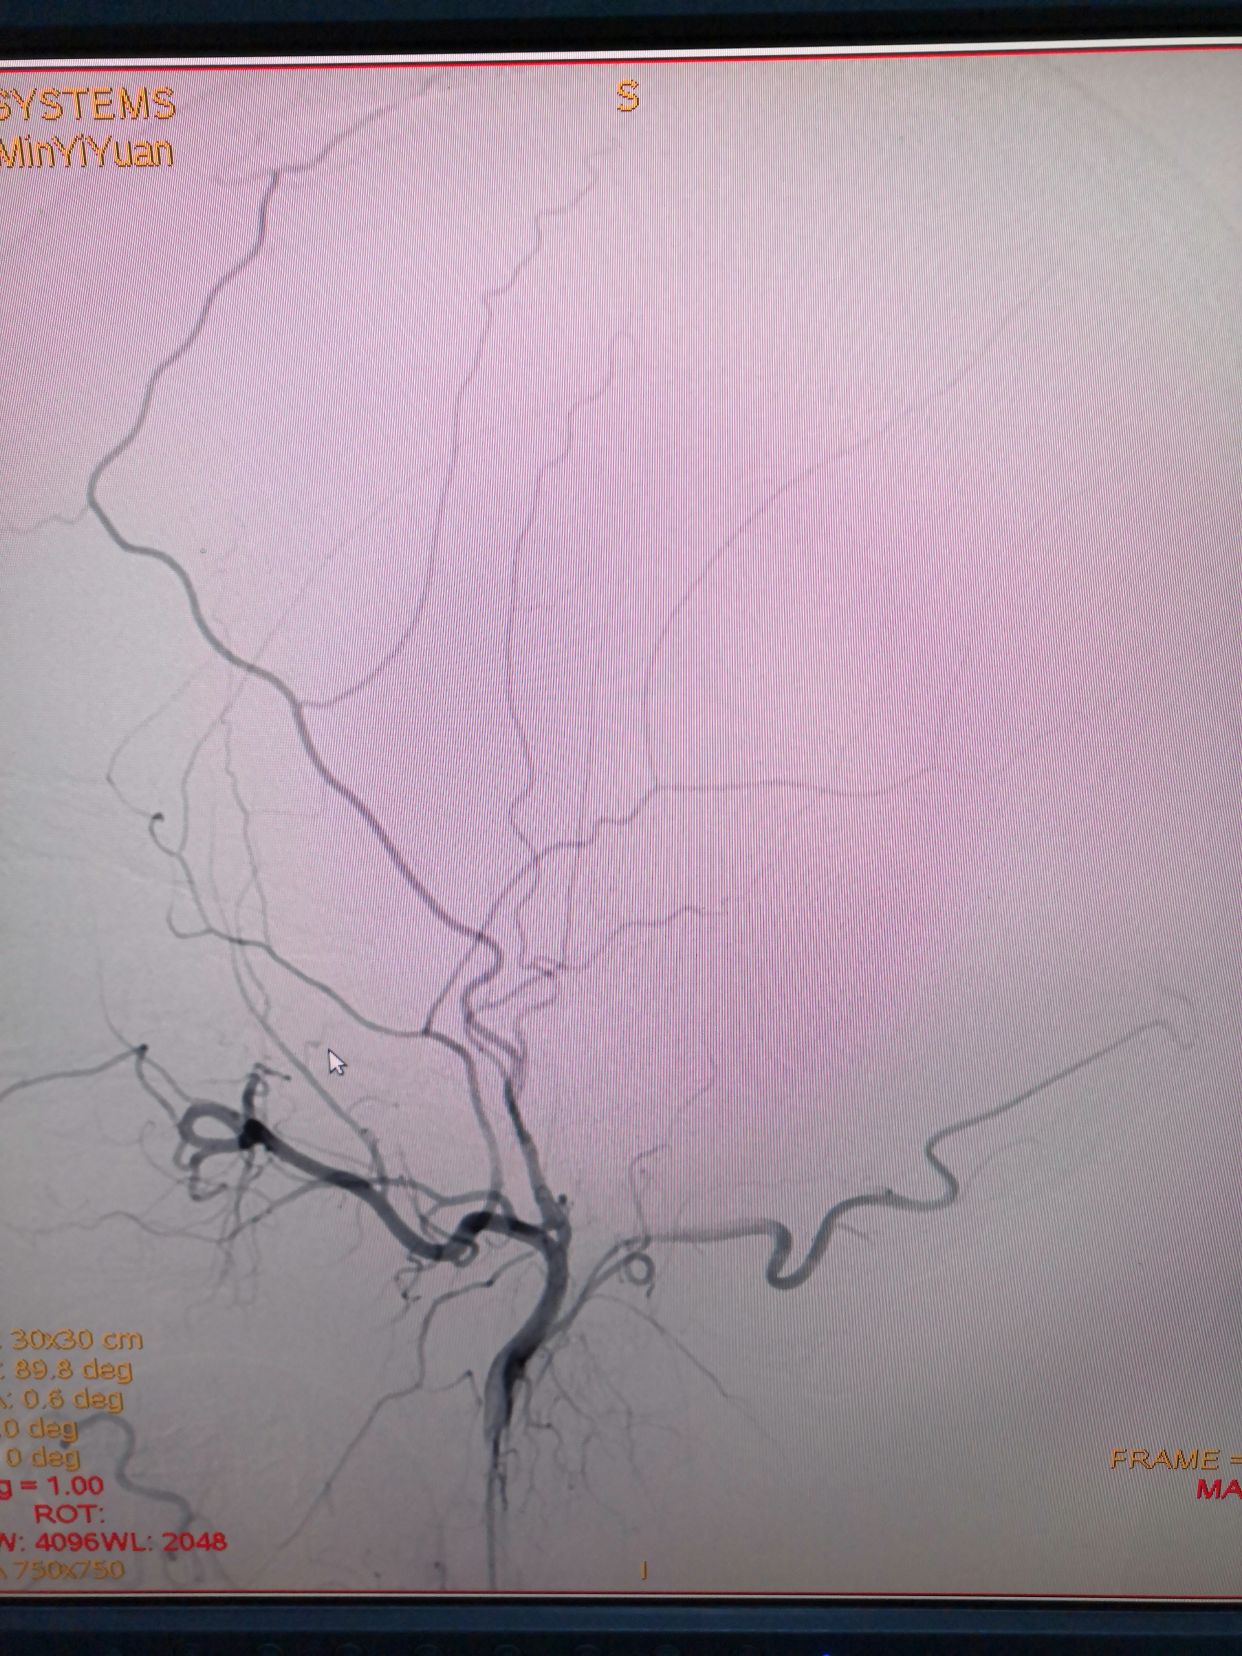

右侧颈内动脉造影正位

侧位